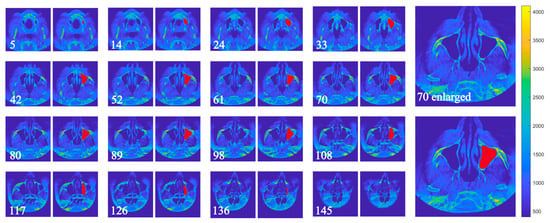

2.2. Algorithm for Detection of the Maxillary Sinus

- Maxillary sinus identification in each image: For a given image, surfaces associated with the sinus volume are determined by checking whether pixels in the upper and lower planes are contiguous with pixels of equivalence classes in the current plane. Let be the set of equivalence classes in plane k; then

- Iterative volume refinement: After each iteration, newly detected pixels are checked for contact with previously undetected equivalence classes in adjacent slices. If such contact exists, the algorithm traverses the images in reverse to incorporate them. This process continues until no new pixels are added. Finally, the images are scanned in normal order to associate any remaining pixels with the sinus volume.